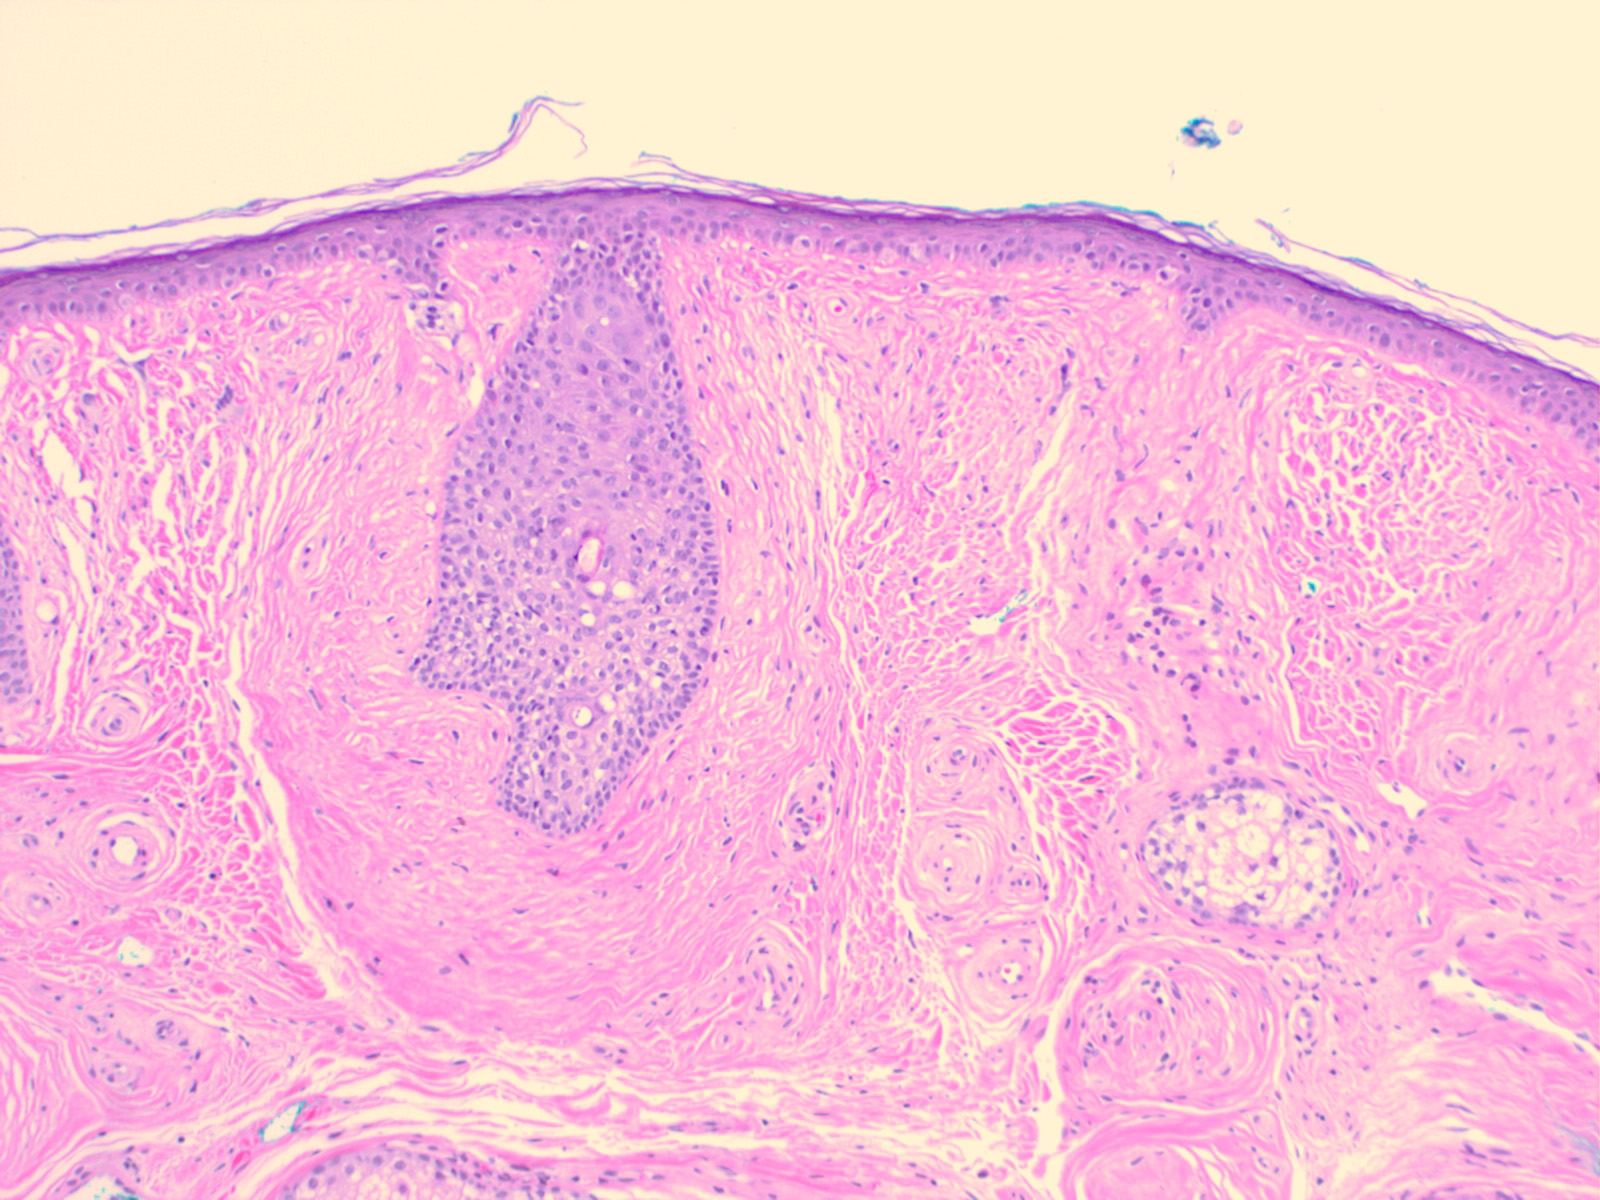

Perifollicular fibroma = الليفوم حول الاجربة الشعرية